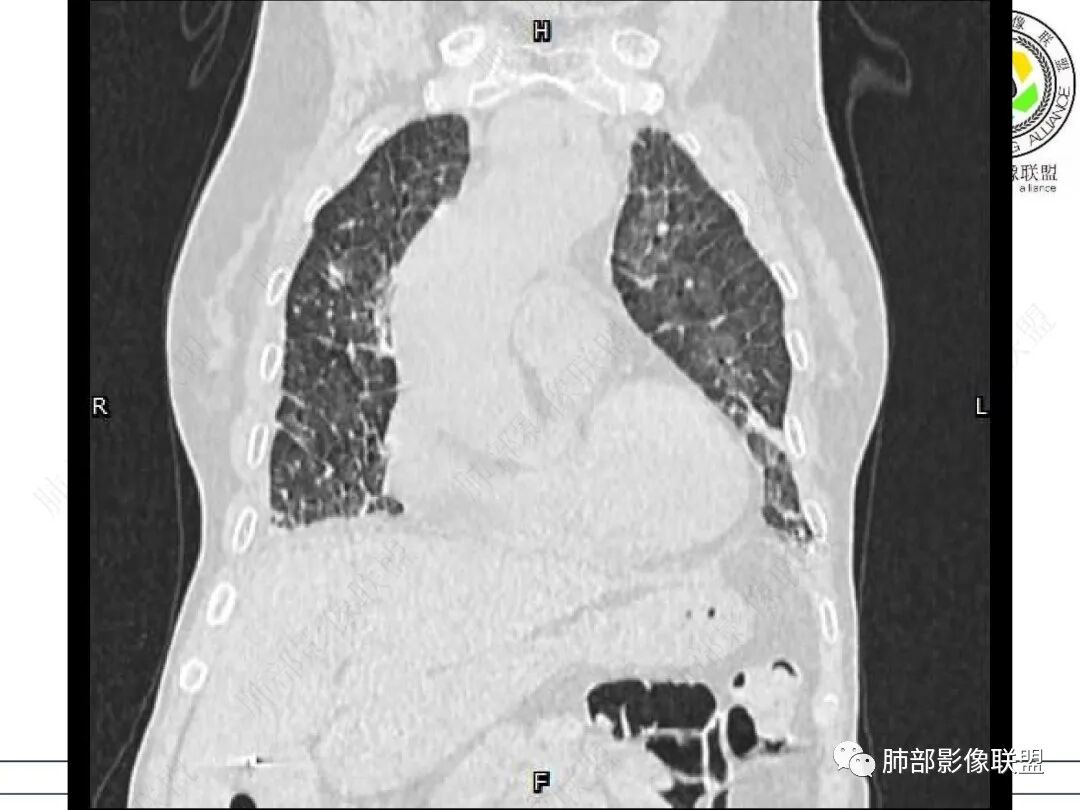

两肺叶后肋膈角区见多发蜂窝状结构破坏表现,双肺叶小叶间隔增厚,左肺上叶后段及舌段和右肺中叶胸膜炎性肉芽肿特点,双侧胸腔少量积液,有类风湿性关节炎治疗史,结缔组织相关性间质性肺病。

老年女性,类风湿关节炎病史多年。发热。以两肺下叶为主弥漫磨玻璃及网格状透亮影,透亮度减低,局部小蜂窝状改变;两肺胸膜下散在几枚实性病灶;双侧胸腔积液。考虑RA-ILDNSIP

两下肺多发蜂窝状表现,双肺小叶间隔增厚,双肺磨玻璃影及部分炎性肉芽肿表现,双侧胸腔积液,有类风湿性关节炎治疗史,结缔组织相关性间质性肺病。患者C反应蛋白和降钙素原都高,是否合并细菌感染

女,71,外阴疼痛2周,发热1周。类风关、高血压、高血糖、卵巢囊肿、肠粘连、胆囊结石等病史及相关药物治疗史。胸部CT:两肺弥漫磨玻璃,血管束增粗,两下肺后肋膈角多发蜂窝,对称分布,双侧胸腔少量积液,纵隔窗心脏大血管影明显增宽。考虑混合性病变,CTD-ILD,并肺水肿?并PJP?。

双肺下叶多发蜂窝影,双肺小叶间隔增厚,双肺磨玻璃影,双侧胸腔积液,有类风湿性关节炎,考虑结缔组织相关性间质性肺病,合并感染

①影像表现复杂:较弥漫间质性改变,对称磨玻璃密度为主,小叶间隔增厚,有一定重力分布趋势,未见明显纤维化,气囊及蜂窝位于肺边缘,未见典型“月弓征”。心脏影增大,双侧胸腔积液。

这即可见于间质性肺病,也可见于真菌感染(如PJP)、病毒感染,类风湿,以及肺水肿等等。

一般而言,如存在磨玻璃密度影浑浊,有重力分布趋势,肺表面蜂窝影,胸腔积液等等,并不常见于单纯PJP,除非其他因素叠加。

患者存在肺水肿应当是合理的解释。其他旁证还有,心脏影增大,肾小球滤过率降低,双侧胸腔积液等等……